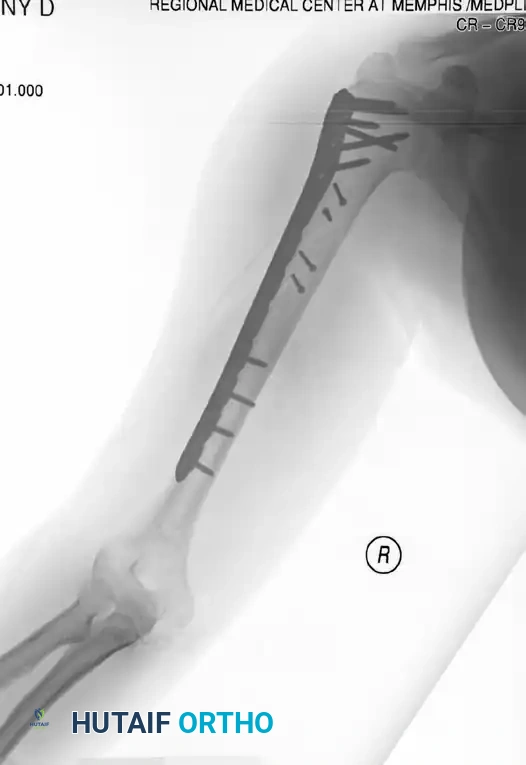

Figure 57-37 A: Displaced humeral shaft fracture.

Figure 57-37 B: After fixation with mini-fragment plate (Eglseder technique) and definitive compression plating.